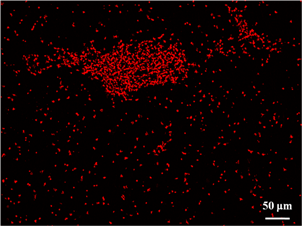

After the successful construction of an ECM-like scaffold, primary human aortic endothelial cells (HAECs) were used to evaluate the scaffold's biocompatibility and its capacity to support the regeneration of a functional endothelium. Our results show that HAECs could easily adhere to the scaffold's luminal surface and form a confluent mono-layer within 24 hr, given an appropriate seeding concentration. In addition, tight junctions between adjacent HAECs were detected within the same time window. This endothelial mono-layer almost completely prevented human platelet adhesion while the bare scaffold induced widespread platelet adhesion and aggregation.

Fig.3 From left to right: HAECs confluent mono-layer; Tight junctions (white arrows) between adjacent HAECs; Platelet adhesion and aggregation on bare scaffold; Platelet adhesion on exposed scaffold (white arrows) in an endothelial mono-layer. No platelet adhesion/aggregation on HAECs mono-layer.

Furthermore, we determined that HAECs were able to produce prostacyclin, a multi-functional factors secreted by native endothelium to prevent thrombosis. The proliferation profile shows that HAECs possessed a strong growth capacity and that the degraded scaffolding materials did not jeopardize the viability of HAECs. The death rates of HAECs within initial 3 days were extremely low, exhibiting no increasing trend.